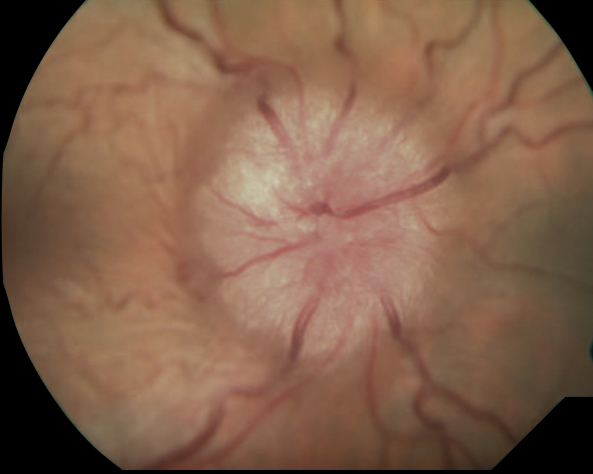

Quais os achados na papilite?

Qual a forma mais comum de neurite em crianças?

Papilite

Quais as causas mais comuns de papilite?